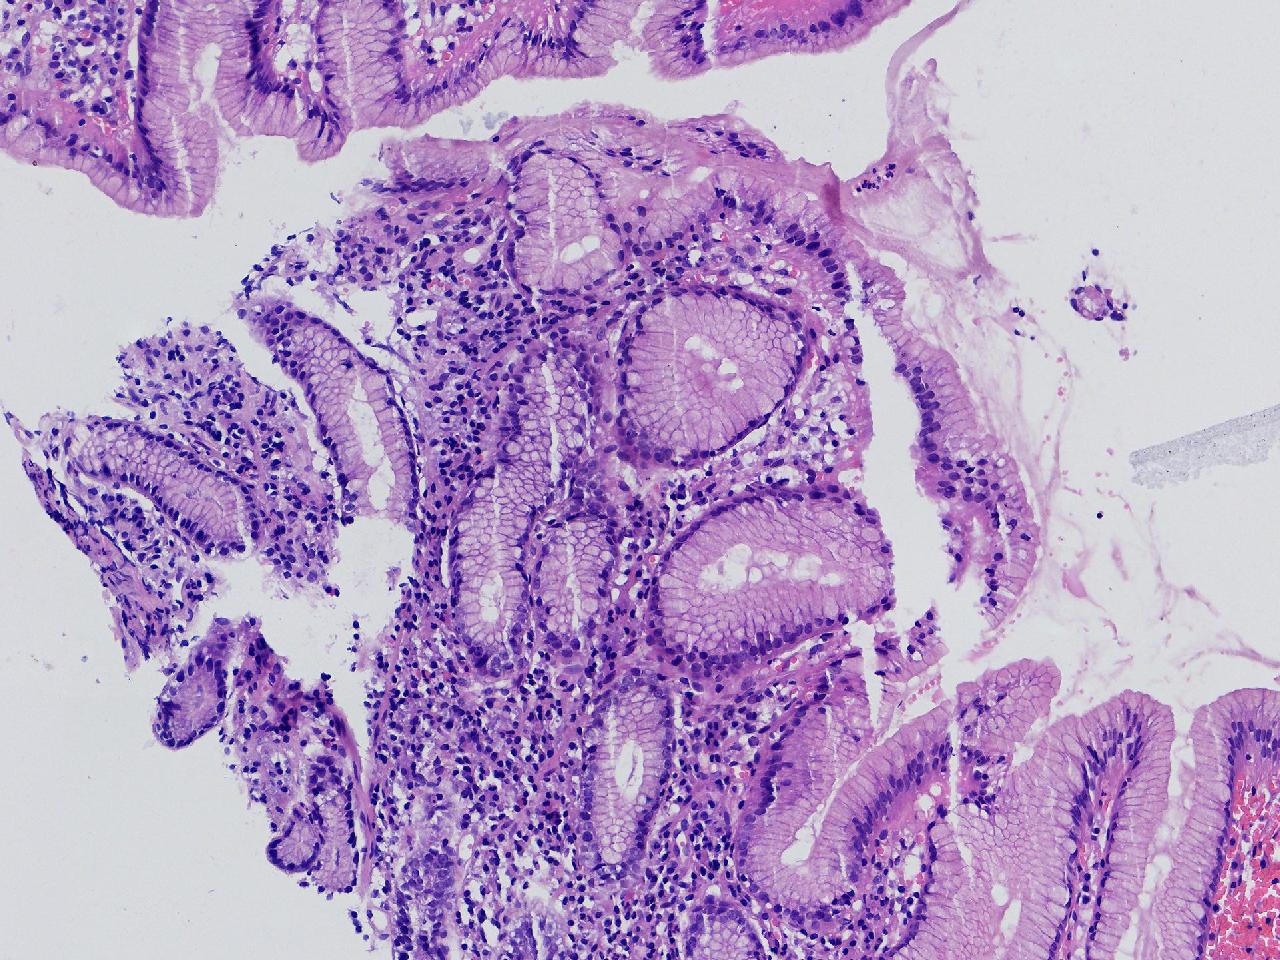

间质内是炎细胞吗?

男,49岁,胃镜活检,胃窦粘膜红白相间,以红为主,后壁见一直径约0.4cm大小片平隆起,表面糜烂,活检1块送检,质软弹性可。

胃窦活检

灰白色不整形软组织1块,直径0.2厘米。

是!还有组织细胞

幽门型粘膜中度慢性炎

是的,主要是淋巴细胞和浆细胞。